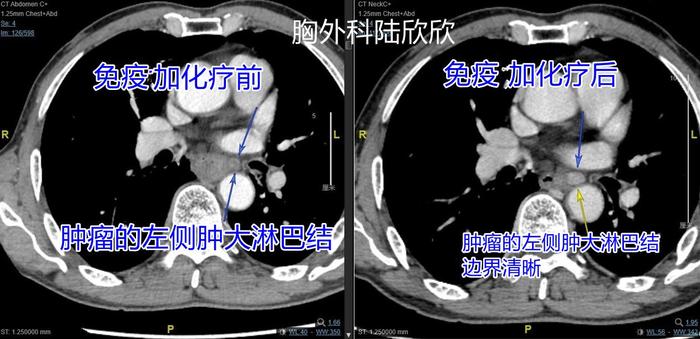

上图,左边的图是化疗加免疫治疗前的图,右边的图是化疗加免疫治疗后的图。可见,治疗前肿瘤左侧的一个增大的转移淋巴结。治疗后此淋巴结较治疗前稍增大,而且边界更加清晰。这个增大是真的,但是最终病理证实淋巴结里面的肿瘤有所减少。